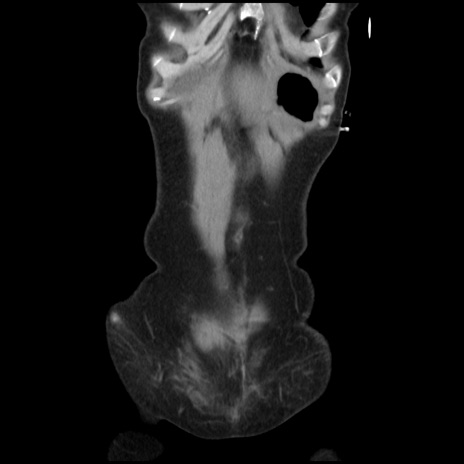

矢状断像